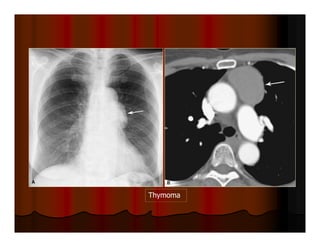

HILUM OVERLAY SIGN: TERATOMA

Thymoma